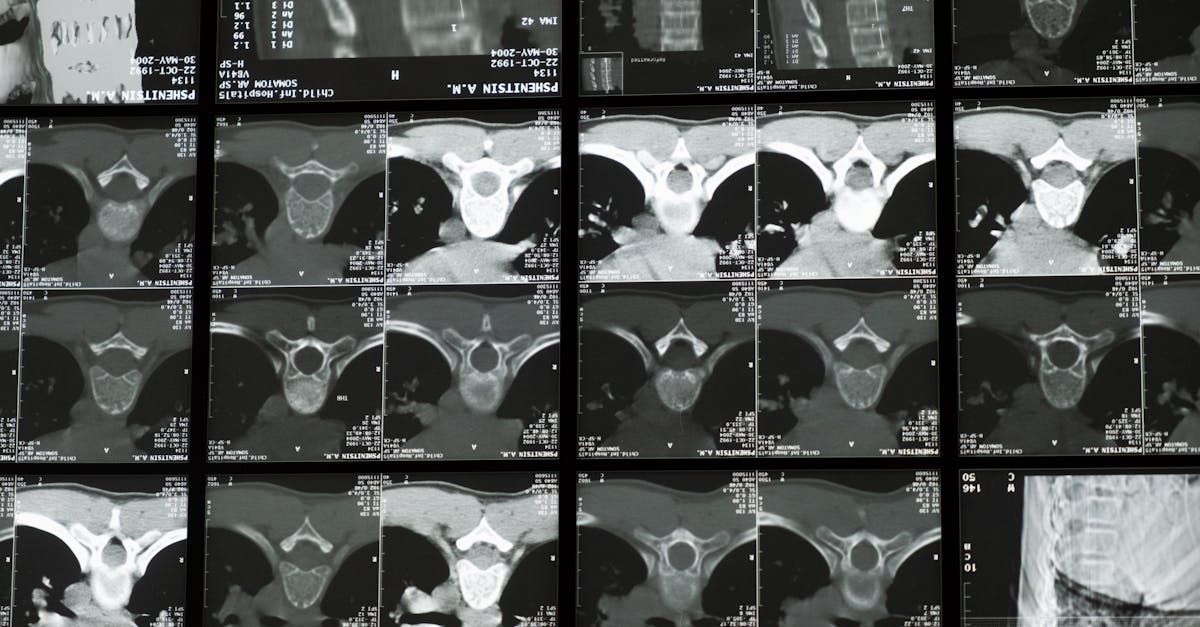

Un diagnostic précis par imagerie, comme l’IRM, doit être établi afin d’évaluer la gravité de la condition et de déterminer l’éligibilité à ce type de traitement.